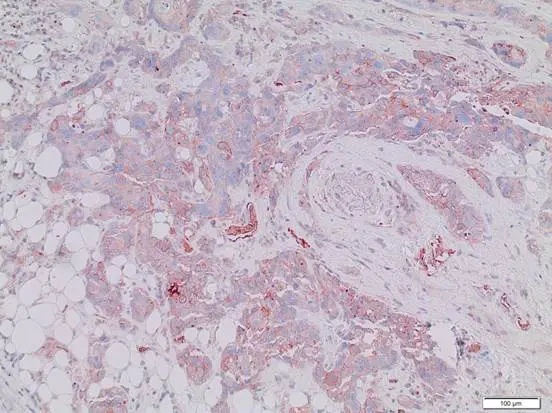

Breast cancer cells in glandular breast tissue. The cell walls stained in brown show the presence of stem cell markers CD47 or MET, respectively.

Scientists from the German Cancer Research Center (DKFZ) and the Institute of Pathology of Heidelberg University Hospital have examined tissue samples from 255 breast cancer tumors in search of two different stem cell markers. Cases where both of these markers were detected were correlated with a dramatic reduction in the life expectancy of patients. Conversely, patients whose tumors exhibited neither of the two markers survived about 10 years longer. The scientists now plan to investigate whether these two markers, found on the surface of breast cancer stem cells, can be used as targets for breast cancer treatments.

By one year ago, the team had screened the blood of breast cancer patients for cancer stem cells, which are considered responsible for the development of metastases. Only a small, specific population of cancer cells that circulate through the body are truly capable of developing metastases, the scientists discovered. Such “metastatic" stem cells exhibit two stem cell markers, proteins called CD47 and MET, on their surfaces. The more of these cells that were detected in a patient’s blood, the higher the rate of metastasis in the patient. “We now hope to find out whether these stem cell markers and, thus, metastatic stem cells, can be detected in the primary tumors in the breast, and if so, whether their presence influences a patient’s chance of survival," Trumpp says.

His lab collaborated with Irene Baccelli of HI-STEM and Albrecht Stenzinger of the Institute of Pathology of Heidelberg University Hospital, who comes from the department headed by Professor Wilko Weichert. The two are first authors of a study which tested 255 breast cancer samples for the stem cell markers CD47 and MET. Subsequently, they compared the presence of the markers with survival data obtained from patients. They discovered that tumors which exhibited both markers simultaneously were strongly associated with a reduction in the life expectancy of patients.

“The results of the study were clear: Patients in whose tumors we detected both types of markers survived on average 10.3 years less after a diagnosis than patients whose tumors exhibited neither CD47 nor MET," Wilko Weichert says. “The presence of these two surface molecules can therefore serve as an indicator for the life expectancy of breast cancer patients." So far the findings are restricted to a particular type of breast cancer, known as estrogen-receptor-positive tumors.